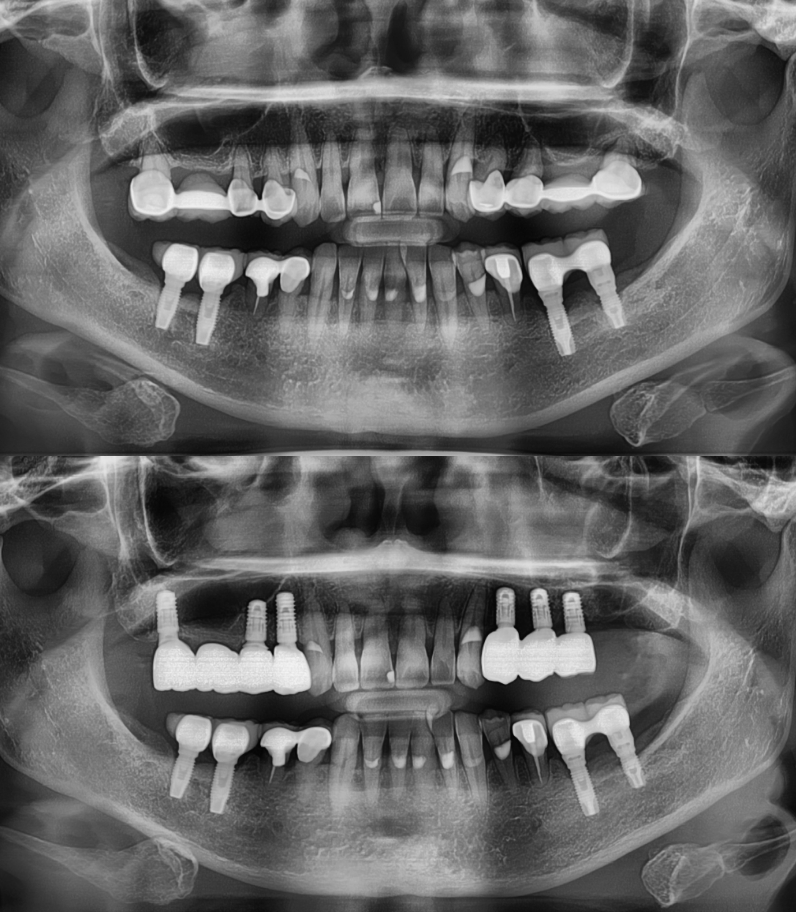

임플란트 전/후

실제 케이스

성공적인 임플란트 치료는 세밀한 분석과

그에 맞는 치료가 중요하기에

다수의 치료 경험을

보유한 의료진이 상주한 곳에서 시작하시기 바랍니다.

임플란트

환자 성함 : 김**

치료기간 : 2023.05 - 2024.06 (1년 1개월)